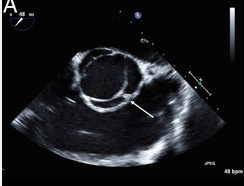

Two-Dimensional evaluation of AoV

WHAT SETTINGS

WHAT VIEWS

• Obtain careful, high resolution imaging focusing on the aortic valve in both harmonics and fundamental modes in the parasternal long axis view and short axis view

o Use magnification (zoom)

severe AI

Quadracusp aortic valve-clover

severe AI